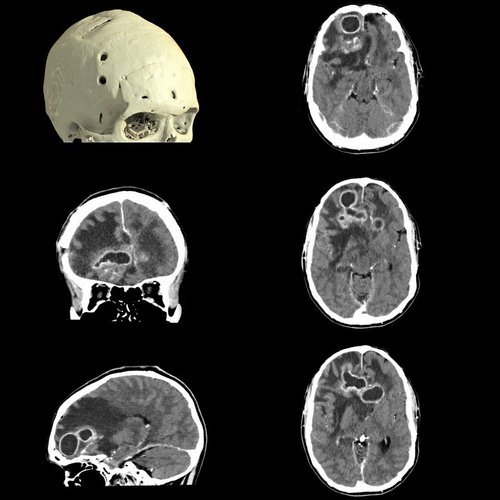

Die Stroke-Evaluation-Plattform von Canon Medical erlaubt die Durchführung einer Perfusionsbildgebung des gesamten Gehirns und eine digitale 4D-Subtraktionsangiographie des intrakraniellen Kreislaufs in nur einer Minute. Mit der Unterstützung durch die 4D-Software wird die Bewertung von Fluss- und Perfusionsfehlern in weniger als fünf Minuten ermöglicht.